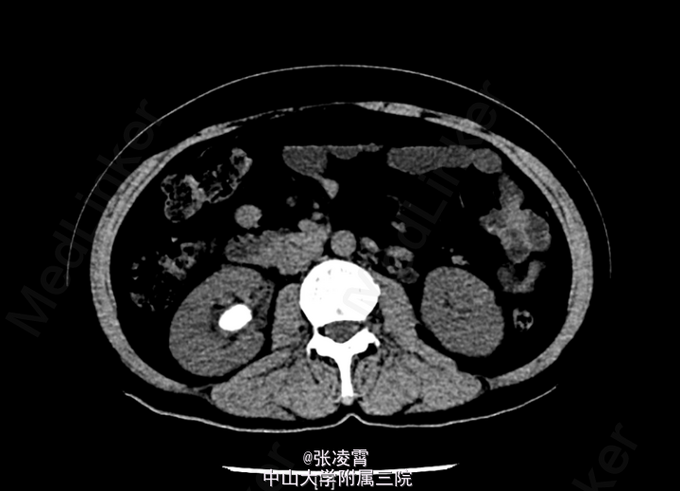

查体:双侧肾区叩击痛(+)。 血常规:白细胞 12.03 ×109 /L;中性粒百分比0.758 尿常规:白细胞 1647.3个/L;红细胞 1135.4个/L 大便常规,凝血四项,生化全套,术前八项等未见明异异常。 KUB示:右肾结石,左侧输尿管下段结石。 CT提示:右肾结石并右肾积水,左侧输尿管下段结石并输尿管扩张。 胸片,心电图大致正常。

诊断:1、左输尿管结石并左肾盂积水;2、右肾结石并积液。 入院第二天最高体温 39℃,目前予以舒普深 3.0 Bid 抗感染治疗三日后,体温正常,复查尿常规白细胞42个/L。予完善相关术前准备后行左侧输尿管镜下钬激光碎石取石术+右侧PCNL术。手术过程顺利。术中出血约30ml,耗时3h。